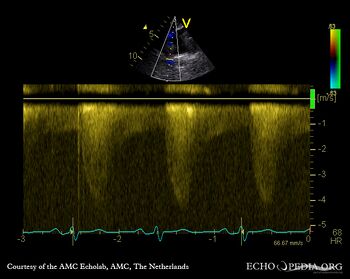

Coarctatio aortae

Courtesy of: AMC Echolab, AMC, The Netherlands

E00361.gif E00362.gif

Suprasternal view Suprasternal view: Collor Doppler, high velocity flow in descending aorta